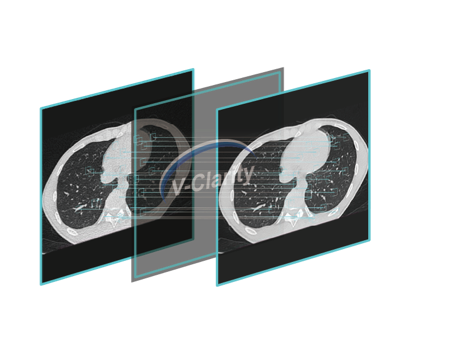

Wide detector expands single-rotation coverage, shortens exam time, reduces motion artifacts, decreases radiation dose, and saves tube exposure time while effectively lowering operating costs